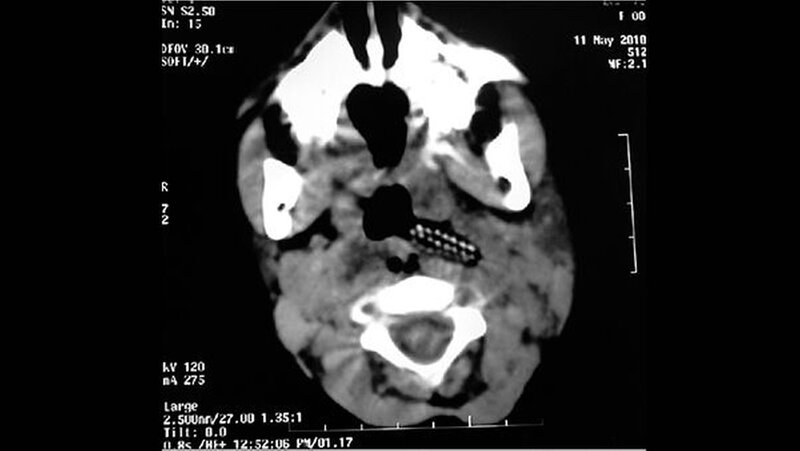

Da es sich um ein Kind handelte, kam eine Rachen-Kehlkopf-Spiegelung nicht in Betracht. Röntgenaufnahmen des Halses und der Brust ließen keine signifikanten Auffälligkeiten erkennen. Die Computertomografie (CT) des Halses zeigt, wie der Zahnbürstenkopf mit samt der Borsten dein den linken Parapharyngealraum eindringt (Abbildung 1).